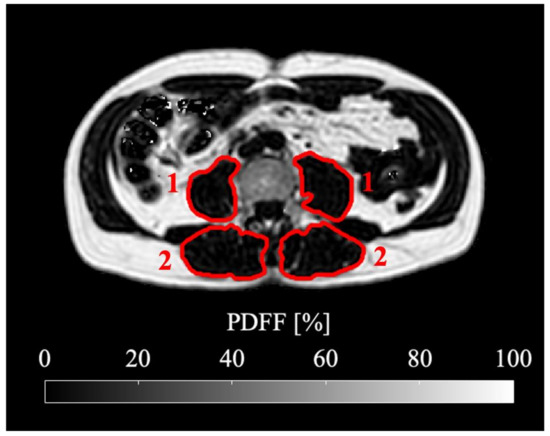

During the follow-ups, the patients lost on average BMI points of 2.11 kg/m2 ± 1.99, (range, −6.11–1.38). In the analyzed skeletal muscle, there was an average loss of total volume, fat volume and contractile tissue volume. A representative PDFF map of a longitudinal scan is shown in Figure 2. Maximum changes (i.e., in case of more than one follow-up, the maximum change in comparison to the baseline) of PDFF (absolute) and skeletal muscle parameters (relative) are visualized in Figure 3 and Figure 4. Maximum relative changes of erector spinae muscle volume and contractile tissue volume showed a significant spatial variation when performing regional analysis for a proximal, middle and distal muscle section. On average, both muscles lost muscle volume, contractile tissue volume and fat volume. A significant maximum relative change of muscle volume was observed for the whole psoas and erector spinae muscle (−9.2%, p < 0.01; −7.7%, p < 0.01). Both middle and distal muscle sections of psoas and erector spinae muscle exhibited significant relative maximum change of muscle volume (psoas: −7.6%, p = 0.01, −15.2%, p < 0.01; erector spinae: −8.1%, p < 0.01, −15.0%, p < 0.01). On average, a significant relative maximum change of contractile tissue volume for the whole psoas and erector spinae muscle was observed (−8.9%, p < 0.01; −6.2% p = 0.02). The middle and distal muscle sections of both muscles underwent a significant relative maximum change of contractile tissue (psoas: −7.4%, p = 0.01, −15.5%, p = 0.03; erector spinae −9.0%, p < 0.01, −14.8%, p < 0.01). A significant relative maximum change in fat volume was observed in the psoas middle muscle section (−9.1%, p < 0.05) and erector spinae distal muscle section (−14.3%, p < 0.01).

Figure 2.

Representative PDFF maps of the psoas and erector spinae muscles (marked in red) of the same patient (male, 56 years old, BMI at baseline 28.6 kg/m2, BMI at follow-up 24.2 kg/m2, suffering from adenocarcinoma of the esophagogastric junction) are shown. Baseline scan is on the left, third follow-up scan after 218 days on the right. Mean psoas PDFF at baseline: 12.02%, mean erector spinae PDFF at baseline: 16.69%, mean psoas PDFF at follow-up: 8.62%, mean erector spinae PDFF at follow-up: 14.85%.